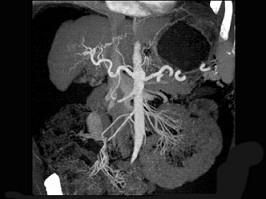

下列图像最可能的诊断是 ( )A.肝脓肿B.肝囊肿C.肝血管瘤D.原发性肝癌E.肝炎肝硬化

问题 下列图像最可能的诊断是 ( )

选项 A.肝脓肿 B.肝囊肿 C.肝血管瘤 D.原发性肝癌 E.肝炎肝硬化

答案 E